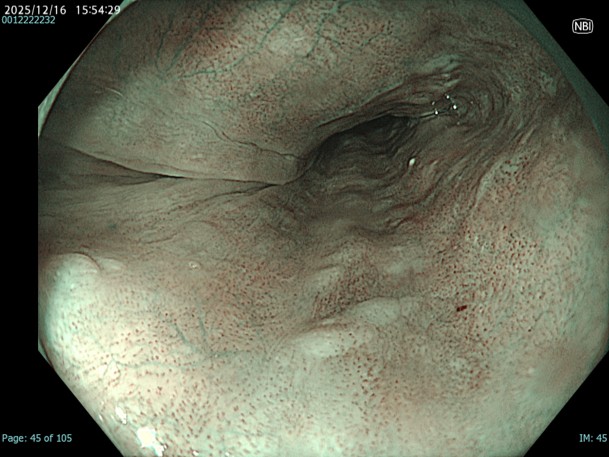

• NBI+TXI観察(中遠景)

切替前 NBI強調設定:A8

NBI+TXIレベル:高

図6

TXIを重ねる事で周囲粘膜の血管透見が向上し、病変の境界がより明瞭になる。画面の9-12時ではNBIでは病変が悩ましいが、この画像では非腫瘍性粘膜である事が明らかである。